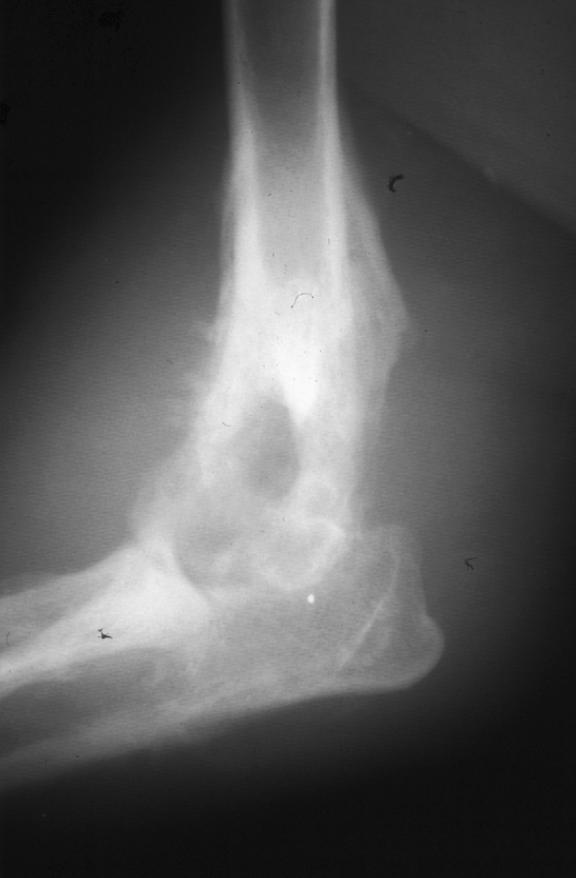

Which radiographs show an active vs. inactive pattern of periosteal reaction?

Left 2 radiographs: inactive; smooth, well defined margins

Right 2 radiographs: active; fuzzy, less sharp margins